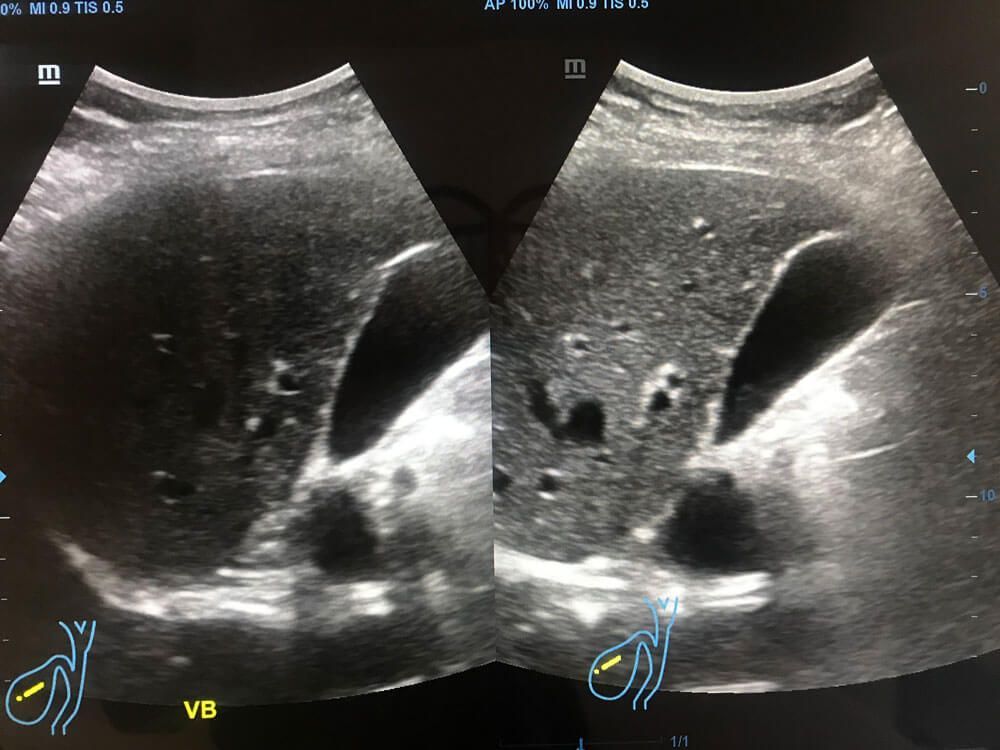

Realizamos

ultrasonidos

convencionales, gestacionales, pediátricos, especializados, entre otros. También aplicamos estudios con

elastografía,

la cual es una herramienta innovadora que permite valorar la rigidez de los tejidos de

mamas, tiroides

y

tejidos blandos.